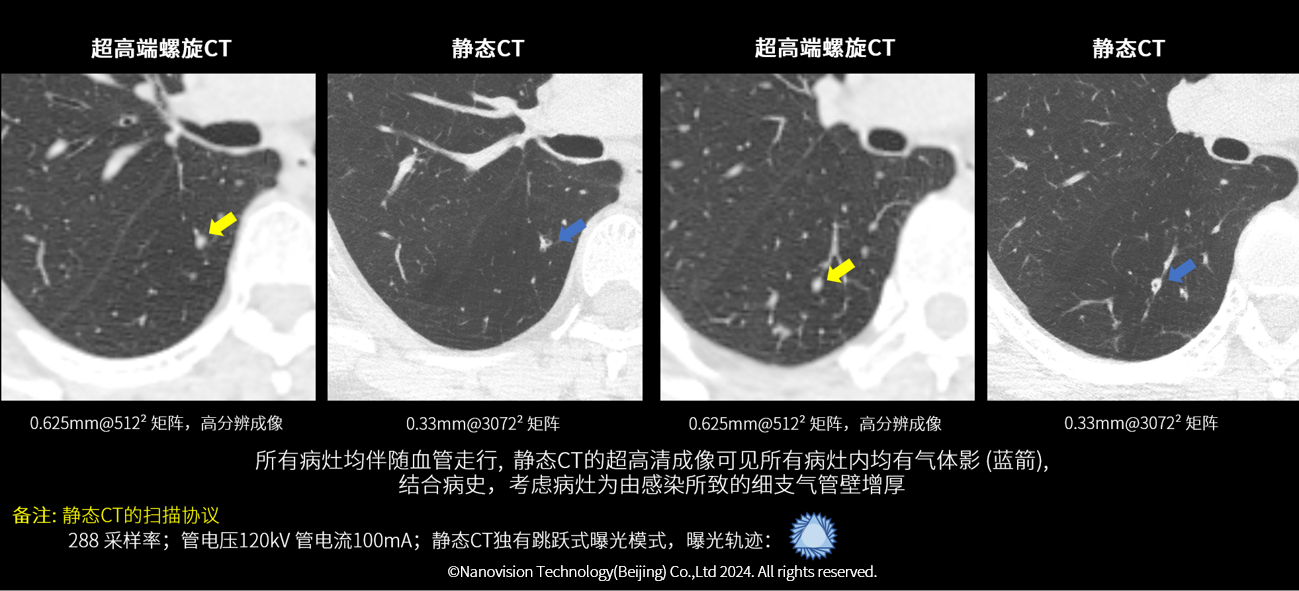

62岁女性, 肺内多发结节样病灶比较